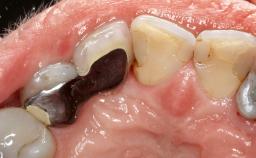

In this case, Nicola Zitzmann describes the sudden loss of a previously well-osseointegrated implant that had been in healthy function for 5 years. The case includes recommendations for occlusion and function of implant restorations. A 74-year-old patient had received implant-fixed dental prostheses in the maxilla in 2008, and in the right mandible three years later. His tooth loss was mainly related to recurrent caries associated with hyposalivation as a potential side effect of his cholesterol-lowering medication.